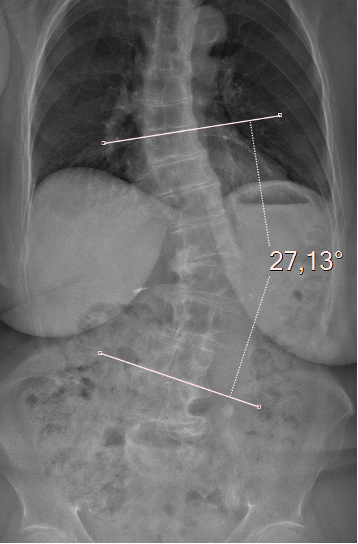

Une scoliose est une déformation de la colonne vertébrale dans les 3 plans de l’espace. C’est une pathologie fréquente chez l’adulte, probablement sous-estimée, qui toucherait environ 38 % des personnes après 60 ans. Les femmes sont plus souvent atteintes que les hommes.

- Soit la scoliose existait déjà dans l’enfance. Elle peut rester stable tout au long de la vie ou s’aggraver progressivement (de 1° par an environ). C’est ce que l’on appelle la scoliose idiopathique de l’adulte. C’est pour cette raison qu’il faut continuer à surveiller les scolioses après la fin de la puberté, qu’elles aient été traitées ou non par corset. Le suivi se fait en général tous les 5 ans par une consultation médicale et une radiographie.

- Soit la scoliose apparait vers 50 ans autour de la ménopause. C’est ce que l’on appelle la scoliose dégénérative. Elle est souvent à l’origine de douleurs et de fatigue du dos, parfois de sciatique. La déformation de la colonne vertébrale est liée à des phénomènes d’instabilité de la colonne vertébrale qui apparaissent au moment de la ménopause (pincement de disque, arthrose, relâchement musculaire). La déformation peut s’aggraver (de 2° par an environ) ; il faut la surveiller tous les 2 ans en faisant une consultation médicale et une radiographie.